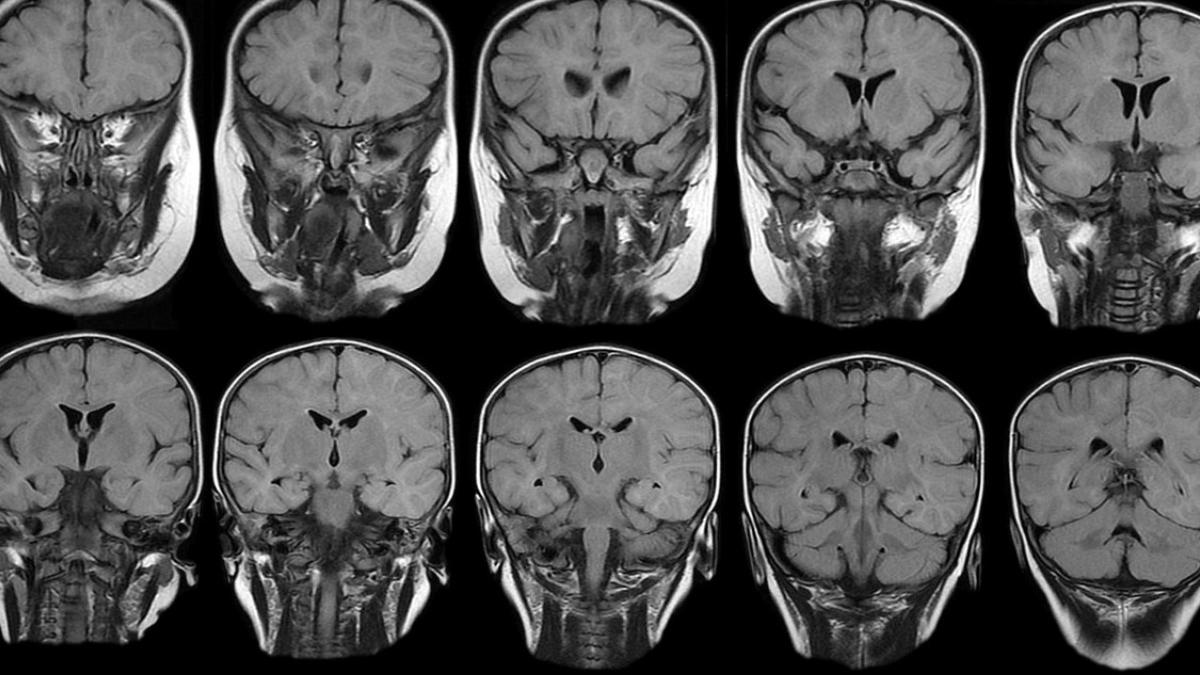

Creierul adolescenților, afectat negativ de lockdown, în pandemie. Au îmbătrânit cu trei ani în câteva luni, arată rezultatele unui studiu06 Dec

Anomalii semnificative la creier, în cazul celor vindecați de COVID-19, descoperite de oamenii de știință21 Noi